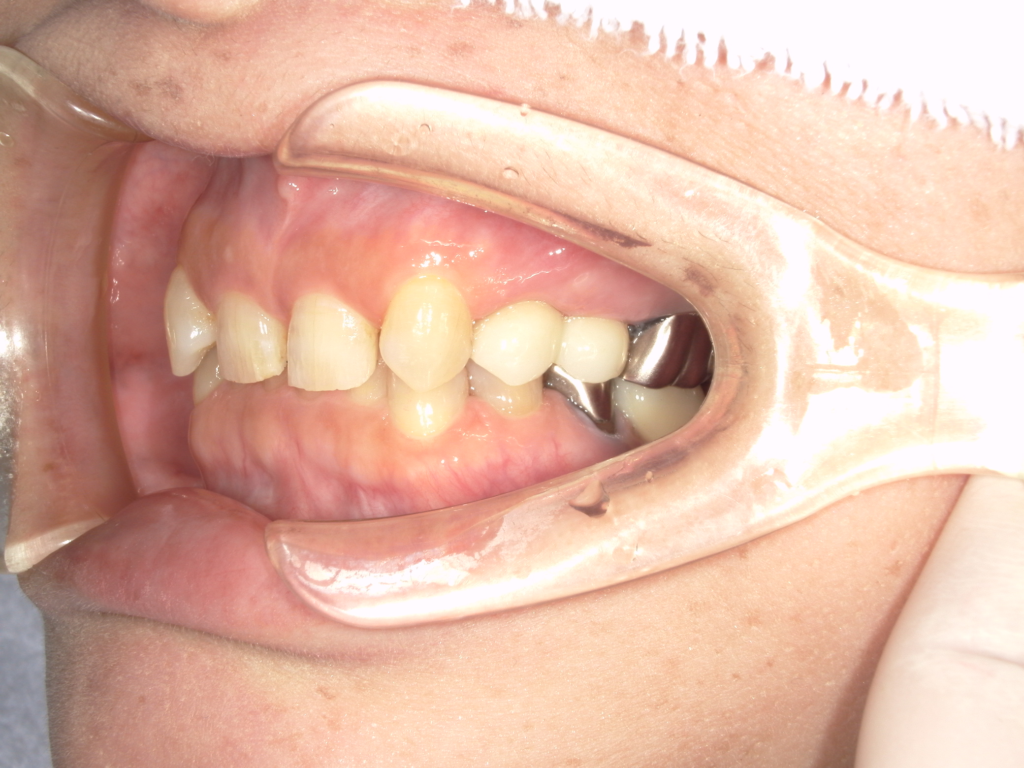

N様 50代 男性 インプラント実例 #37

前歯の4本が、残すのが難しい状況となり、インプラント治療を行いました。

インプラントは前歯に2本埋入し、4本の前歯を作っています。歯を抜くと同時にインプラントを埋入し、仮歯を作りました。その後2ヶ月で、被せ物を入れました。被せ物は、セラミックスで作っています。

治療前

治療後